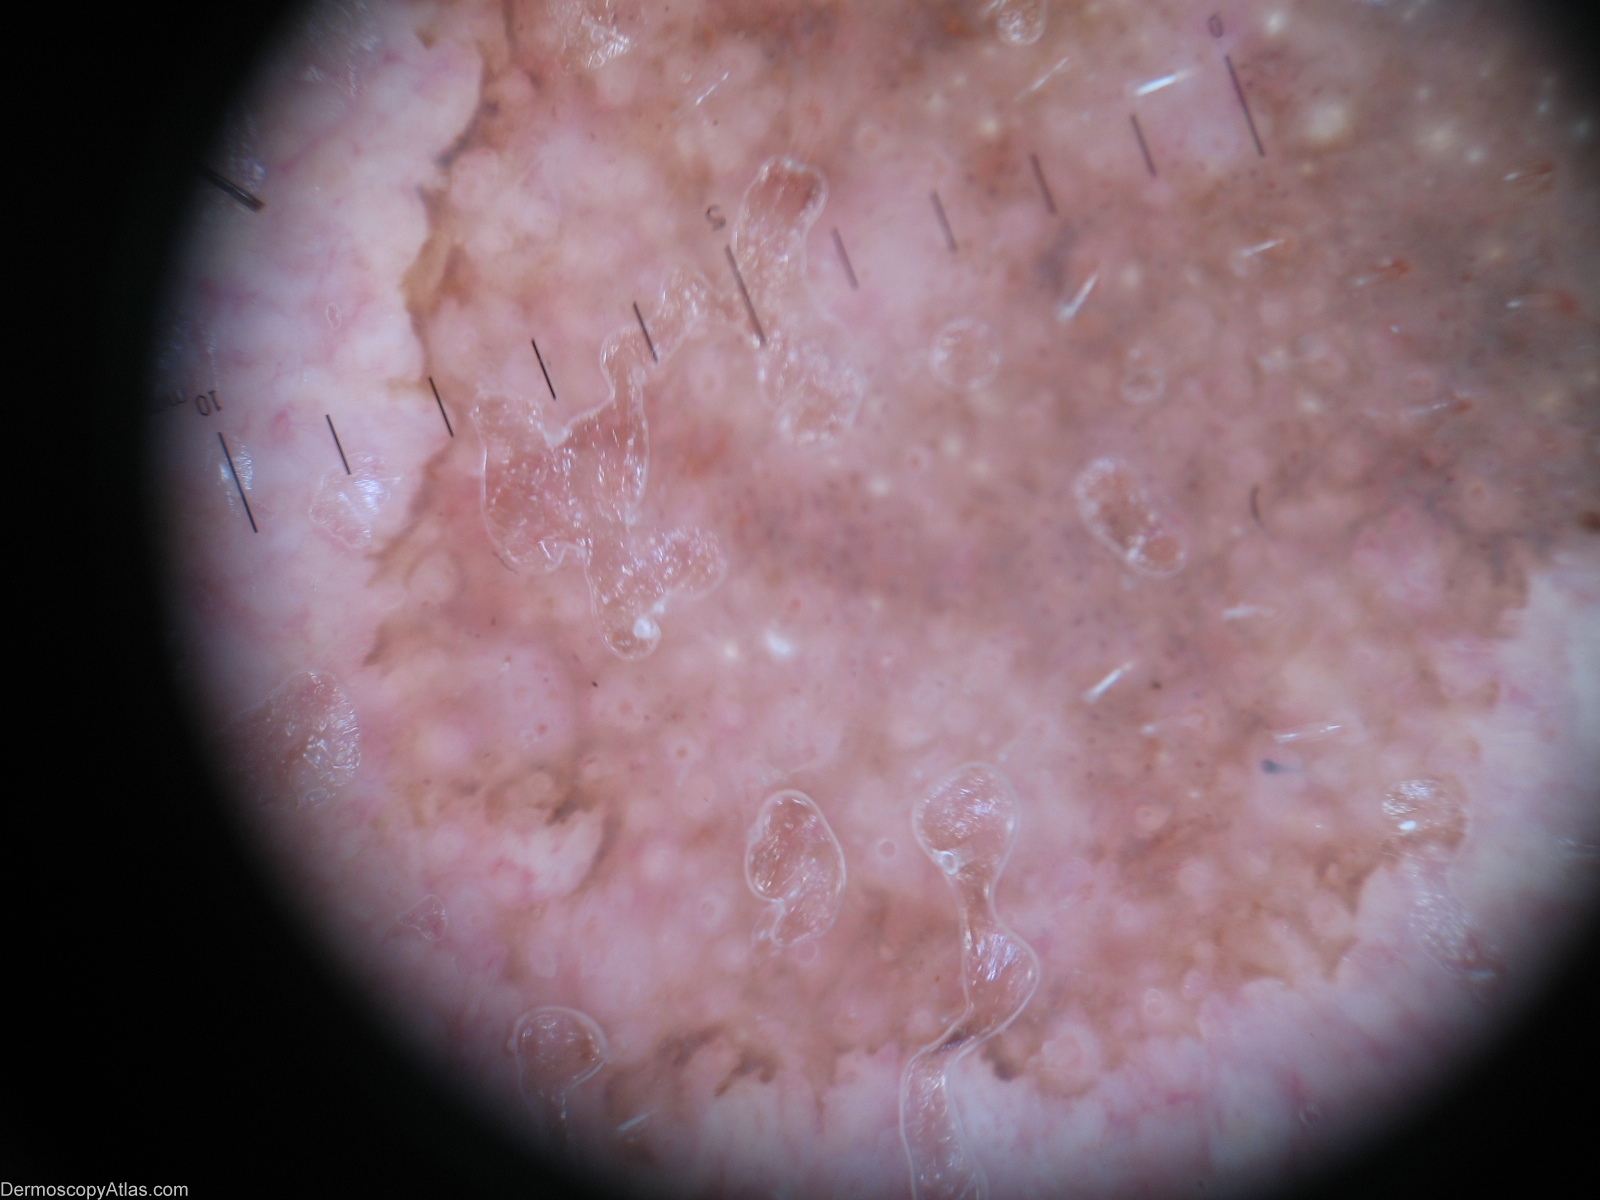

Description: Milia-like cysts and comedo-like openings.

History: Lentigo solar(left part) crossing over with a seborrhoeic keratosis(right part). A 83-year-old man developed an enlarging pigmented patch of his cheek.A biopsy was performed and pathology confirmed the diagnosis of solar lentigo. Dermoscopic description: Right part(seborrhoeic keratosis)- Milia-like cysts,comedo-like openings. Left part(lentigo solar)-sharply demarcated pigmented network and moth-eaten border.